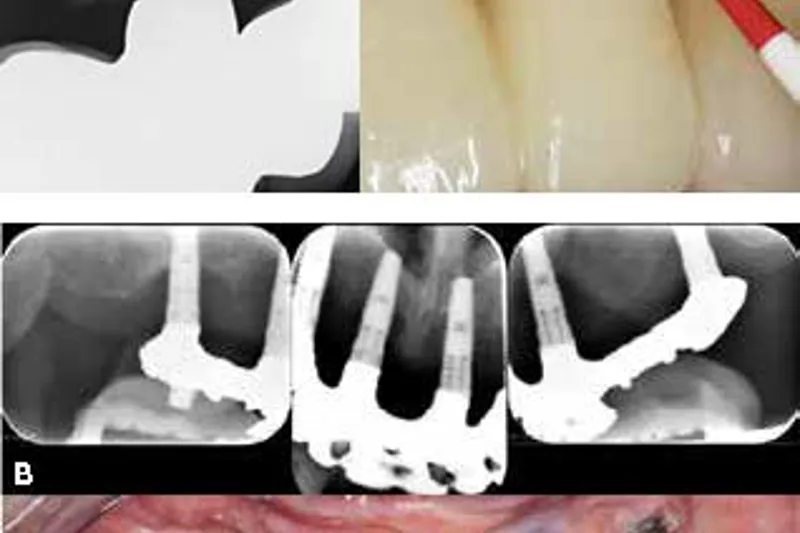

Denne oversigtsartikel sætter fokus på de vigtigste karakteristika ved periimplantær sundhed, periimplantær mucositis og periimplantitis.